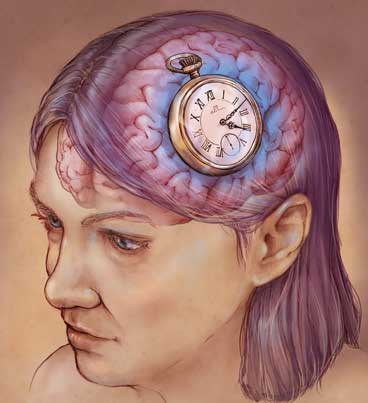

In neurology, there is a number that commands attention—32,000. That’s the number of brain cells that die per second after a stroke, or “brain attack”— precious cells that help you talk to your friends, climb the stairs, button your shirt, swallow your coffee. What would it feel like to suddenly lose even a small portion of them?

Acute treatment is only the first step in stroke recovery. Fortunately, therapists are getting better results with post-stroke rehabilitation than ever. “We used to say to patients, ‘you have three to six months to improve, and after that you can’t expect a whole lot,’ ” says Dr. Richard Zorowitz, chair of physical medicine and rehabilitation at Johns Hopkins Bayview Medical Center. Now, knowledge about the brain’s ability to rewire itself—a concept called neuroplasticity—has encouraged therapists (and patients) to try longer and harder.

“Thanks to the neuroplasticity of the brain—the ability of the brain cells to rearrange their connections, our brain has more capacity than we ever imagined to rewire itself for greater levels of recovery,” says researcher and stroke survivor Dr. Jill Bolte Taylor (read “Life After Stroke”).